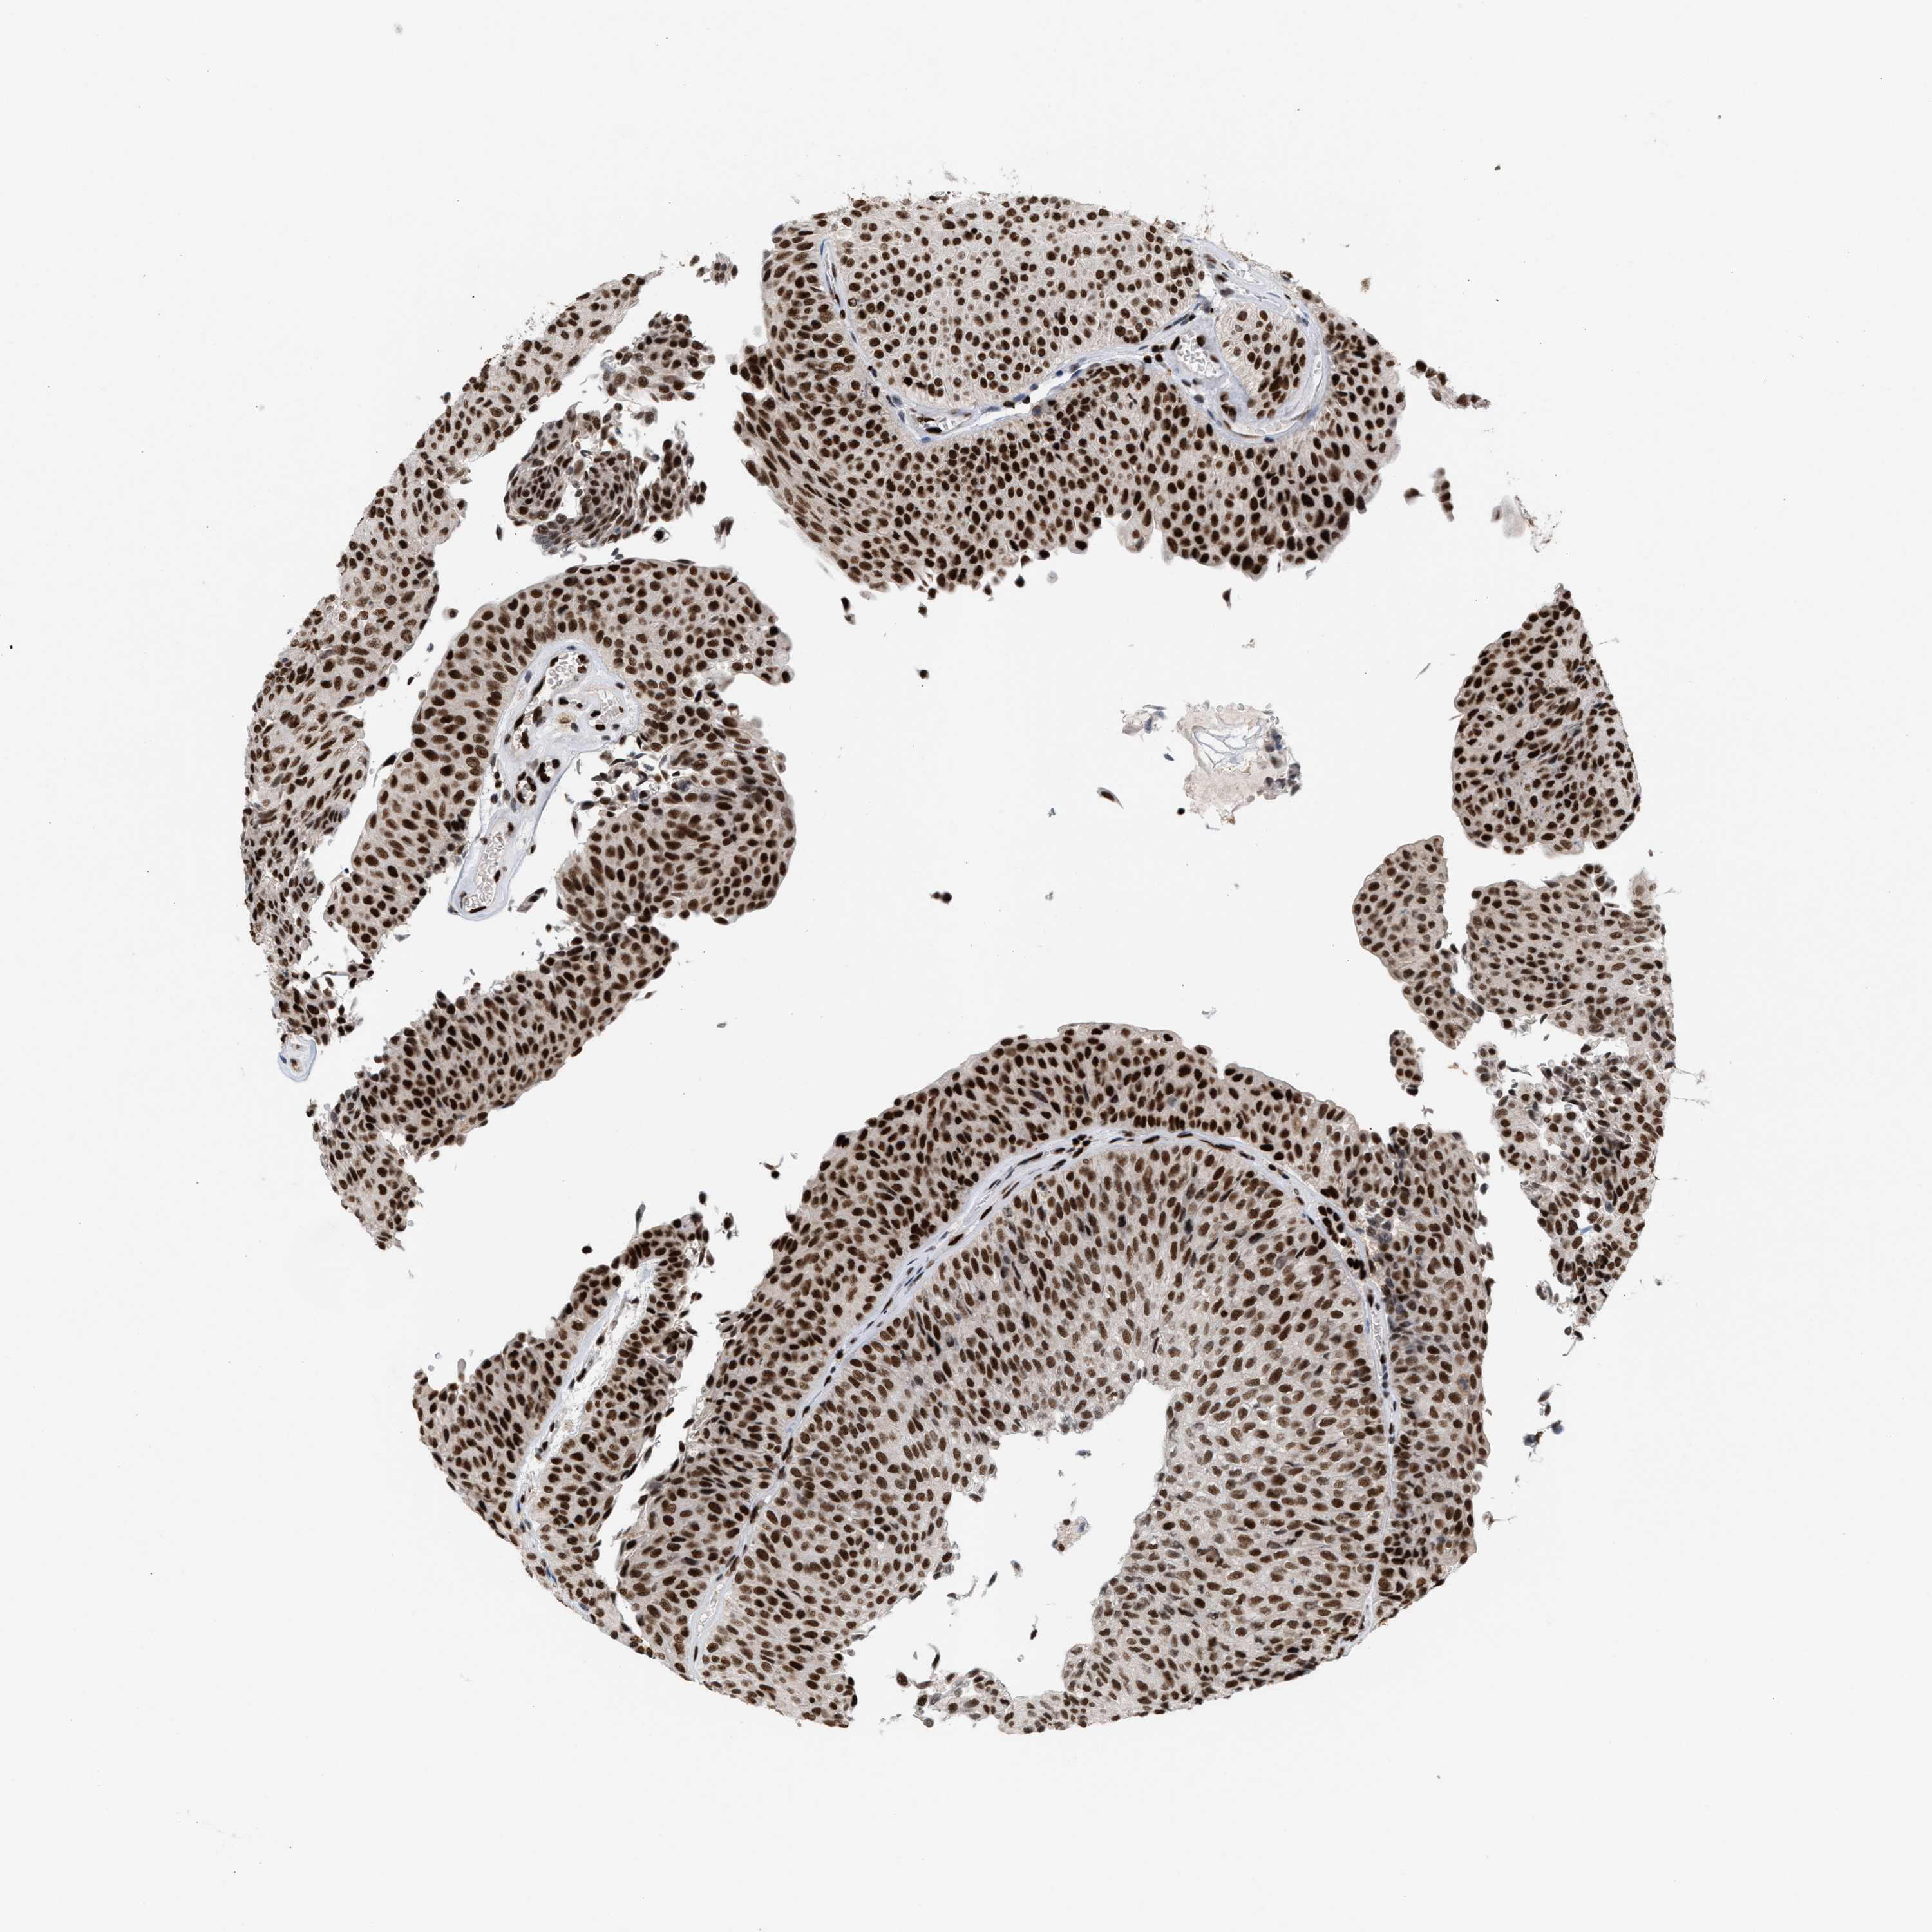

UROTHELIAL CANCER - Protein expressioni

A mouse-over function shows sample information and annotation data. Click on an image to view it in a full screen mode. Samples can be filtered based on level of antibody staining by selecting one or several of the following categories: high, medium, low and not detected. The assay and annotation is described here.

Note that samples used for immunohistochemistry by the Human Protein Atlas do not correspond to samples in the TCGA dataset.

Antibody stainingi

Antibody staining in the annotated cell types in the current human tissue is reported as not detected, low, medium, or high, based on conventional immunohistochemistry profiling in selected tissues. This score is based on the combination of the staining intensity and fraction of stained cells.

Each image is clickable and will lead to virtual microscopy that enables deeper exploration of all samples and also displays staining intensity scores, fraction scores and subcellular localization as well as patient and tissue information for each sample.

Antibody HPA022961

Antibody HPA024457

Staining

High

Medium

Low

Not detected

Intensity

Strong

Moderate

Weak

Negative

Quantity

>75%

75%-25%

<25%

None

Location

Nuclear

Cytoplasmic/membranous

Cytoplasmic/membranous,nuclear

Urothelial carcinoma, Low grade

Urothelial carcinoma, High grade